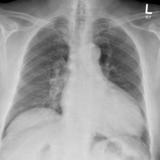

ischemic LV

Date: 01/06/2018

Views: 1359